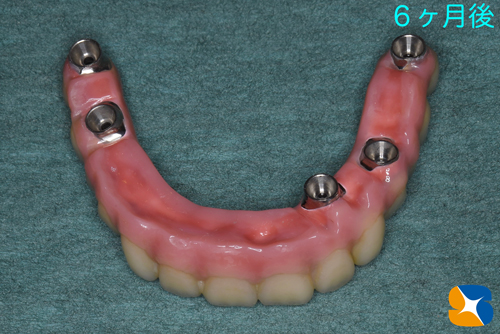

その後、5本のインプラントは確実に定着してくれていましたので、型取りを行いました。

寸分の狂いや隙間が生じないように、丁寧かつ慎重に様々な工程を繰り返しながらネジで完全固定タイプの入れ歯を作成していきます。

完成したネジで完全固定タイプの入れ歯

ネジで完全固定タイプの入れ歯をいよいよ装着していきます。

この夏から使用を始めました。